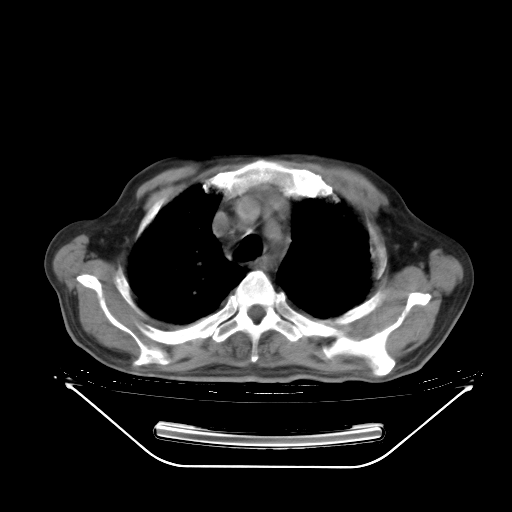

今天复查肺部CT,发现双肺广泛磨玻璃样改变。所以我把3月19日和5月9日相隔50天的肺部CT上传。请大家会诊。

5月9日肺部CT(在4月27日齐鲁医院肺部CT描述部分肺组织磨玻璃样改变,12天后肺组织广泛磨玻璃样改变)

大致读了系列胸部CT:纵隔窗无明显异常,肺窗:从4、27至今:主要是双肺中下野外带可见毛玻璃样改变,目前处于急性肺泡炎阶段,至于原因考虑1、结替组织或胶原血管性疾病所致?2、恶性疾病如恶组在肺部所致的表现或细支气管肺泡癌?3、药物或其它原因如肺蛋白沉着症所致肺泡炎目前不太可能?总之,明天就去请我院的呼吸科、感染科、血液科和临免专家会诊哈。